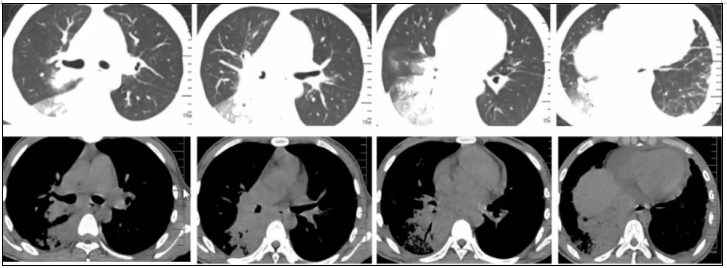

相关文献也提示,TSM的影像学既可以表现为肺内多发结节,也可以有多发空腔样改变,还可以伴有双侧胸腔积液,甚至引起播散性感染,导致腹腔淋巴结肿大,脾大,脾内多发低密度病灶(图17)。有时PET-CT直接回报肺癌、癌性淋巴管炎、纵隔淋巴结转移,或直接回报疑似淋巴瘤。

图片

图17  TSM患者影像学表现

马尔尼菲篮状菌可以引起溶骨性病变。感染性疾病引起溶骨性破坏及坏死并不多见,包括马尔尼菲篮状菌、诺卡菌、放线菌、分枝杆菌等的感染,尤其是NTM。我们曾有一例年轻女性患者,初始诊断马尔尼菲篮状菌,经过治疗,肺部及原有的皮肤病灶显著改善,但患者突发腰痛,就诊时已无法走路(图18)。后经腰椎穿刺活检及组织培养和病理证实既有马尔尼菲篮状菌,又有堪萨斯分枝杆菌。抗感染治疗效果不理想,患者出现截瘫,后续积极抗感染及手术治疗。我们既往可能不太关注感染性疾病累及的骨性病变,而马尔尼菲篮状菌,尤其是HIV阴性马尔尼菲篮状菌,值得我们更多关注。

图18  HIV阴性TSM患者溶骨破坏影像学表现

从上述病例的影像学可以看到,TSM的影像学表现多种多样,包括大片实变、结节、磨玻璃改变、粟粒样病变、肺门或纵隔淋巴结肿大、胸腔积液、空洞、坏死,以及细菌性肺脓肿,内壁光滑,甚至有气液平面,这与我们既往所认识的真菌影像学特征有所不同。研究显示,大部分HIV阳性患者胸部影像学表现形式多样,45.6%表现为斑片状浸润影或局限性肺实变,较少形成空洞病灶(8.0%)。HIV阴性TSM患者胸部影像学表现与HIV阳性患者相似,主要表现为肺部浸润影伴或不伴间质性改变,亦常出现胸腔积液。